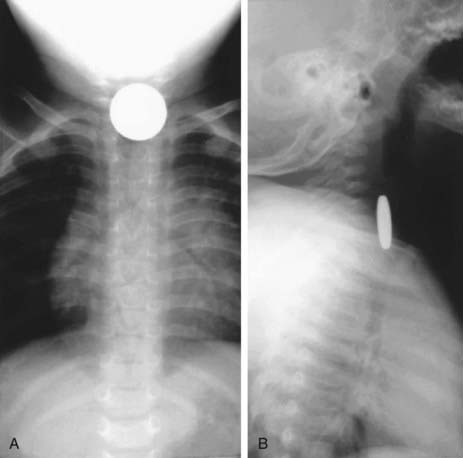

Evaluation of the child with a history of foreign body ingestion starts with plain anteroposterior (AP) radiographs of the neck, chest, and abdomen, along with lateral views of the neck and chest. The flat surface of a coin in the esophagus is seen on the AP view and the edge on the lateral view (Fig. 319-1). The reverse is true for coins lodged in the trachea; here, the edge is seen anteroposteriorly and the flat side is seen laterally. Disk batteries can look like coins (Fig. 319-2) and have a much higher risk of burns and necrosis (Fig. 319-3). Materials such as plastic, wood, glass, aluminum, and bones may be radiolucent; failure to visualize the object with plain films in a symptomatic patient warrants urgent endoscopy. Although barium contrast studies may be helpful in the occasional asymptomatic patient with negative plain films, their use is to be discouraged because of the potential of aspiration as well as making subsequent visualization and object removal more difficult.

image

Figure 319-3 A, Disk battery in esophagus with necrotic debris at burn sites. B, Typical bilateral esophageal burn after removal of disk battery.

(From Wyllie R, Hyams JS, editors: Pediatric gastrointestinal and liver disease, ed 3, Philadelphia, 2006, Saunders.)

Treatment of esophageal foreign bodies usually merits endoscopic visualization of the object and underlying mucosa and removal of the object; therapeutic endoscopy is most conservatively done with an endotracheal tube protecting the airway. Sharp objects in the esophagus, disk button batteries, or foreign bodies associated with respiratory symptoms mandate urgent removal. Button batteries, in particular, must be expediently removed because they can induce mucosal injury in as little as 1 hr of contact time and involve all esophageal layers within 4 hr (see Fig. 319-3). Asymptomatic blunt objects and coins lodged in the esophagus can be observed for up to 24 hr in anticipation of passage into the stomach. If there are no problems in handling secretions, meat impactions can be observed for up to 12 hr. In patients without prior esophageal surgeries, glucagon (0.05 mg/kg IV) can sometimes be useful in facilitating passage of distal esophageal food boluses by decreasing the LES pressure. The use of meat tenderizers or gas-forming agents can lead to perforation and are not recommended. An alternative technique for removing esophageal coins impacted for <24 hr, performed most safely by experienced radiology personnel, consists of passage of a Foley catheter beyond the coin at fluoroscopy, inflating the balloon, and then pulling the catheter and coin back simultaneously with the patient in a prone oblique position. Concerns about the lack of direct mucosal visualization and, when tracheal intubation is not used, the lack of airway protection prompt caution in the use of this technique. Bougienage of esophageal coins toward the stomach in selected uncomplicated pediatric cases has been suggested to be an effective, safe, and economical modality where endoscopy might not be routinely available.